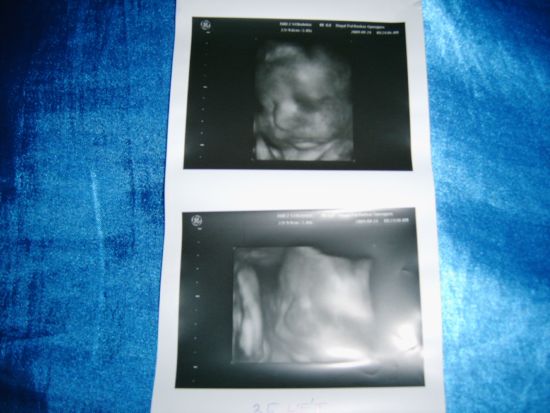

Ma voltunk a 35.-ik heti uh-n! :lol: :lol: :lol: :lol:

Minden nagyon szuper!Pocaklakóm kb 2800 gramm! :lol: (És még van 5 hetünk! :shock: )bízom benne,hogy max 4 kg-nál megáll! :shock: :shock:

A méretei 36 hetesnek felelnek meg.Magzatvíz átlagos,fejvégű fekvés,méhlepény a hátsó falon tapad.A köldökzsinórban az áramlási viszonyok is jók. :lol: :lol: :lol: :lol:

Kaptam egy potya képet.felrakom,bár nem biztos,hogy ki tudjátok venni a pofikáját!A felső kép jobb lett! :lol:

Kép Martin 35 hetesen a pocakban :-)